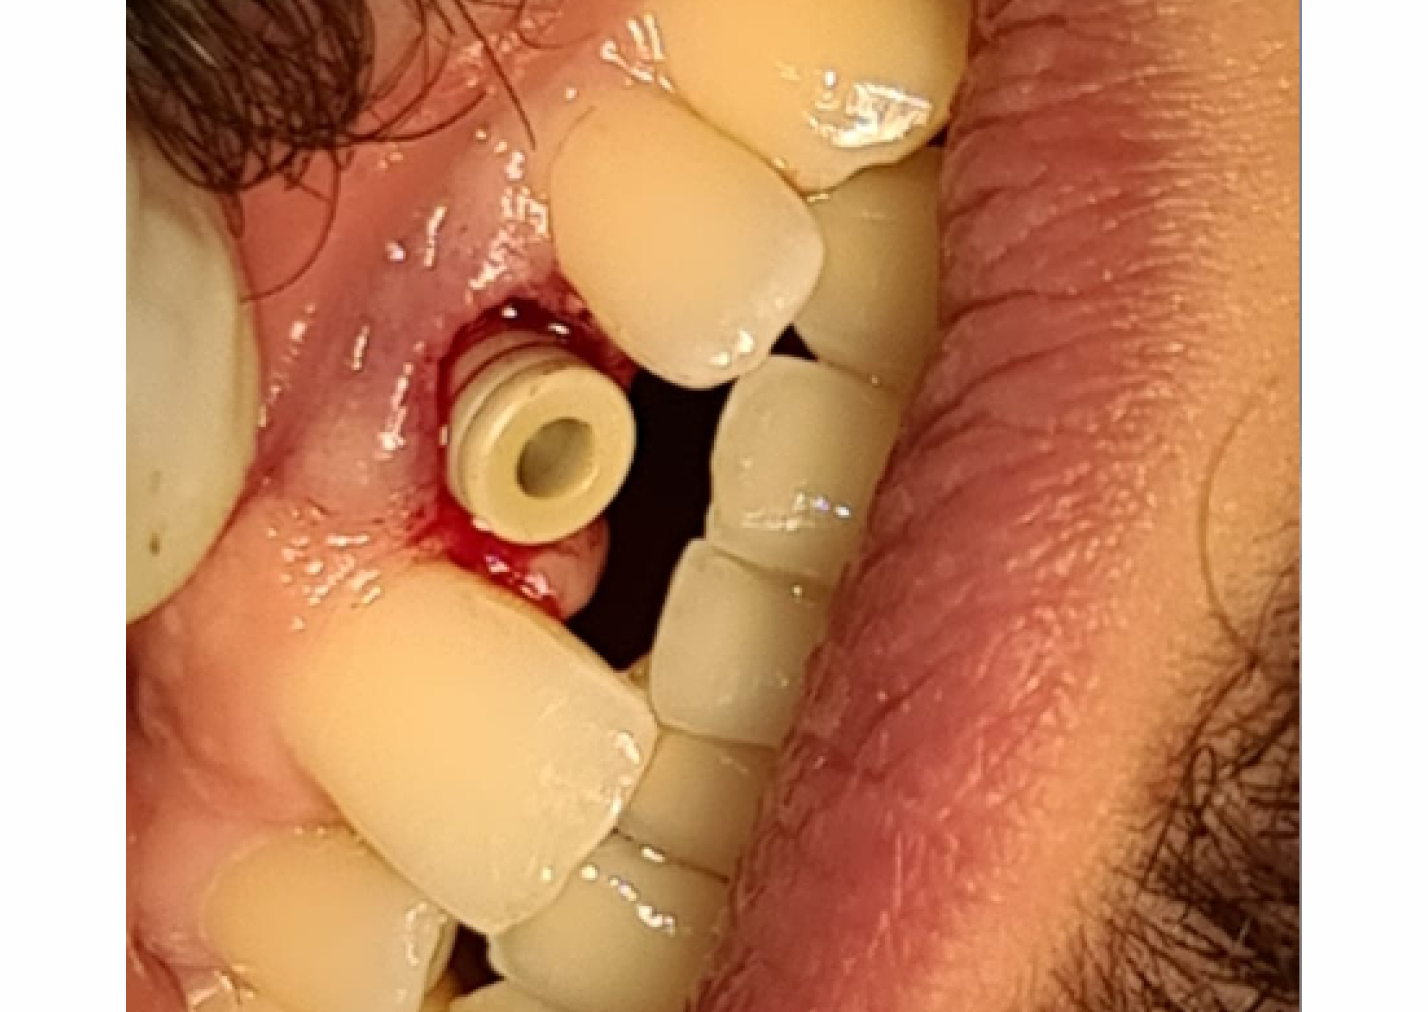

Immediate Loading of Naxis Implant with Simultaneous Restoration

Immediate loading of dental implants, particularly in the aesthetic zone, poses unique challenges and requires meticulous planning to ensure successful outcomes. This case report presents the management of a male patient requiring aesthetic zone restoration through Naxis implant placement with simultaneous restoration following tooth fracture.